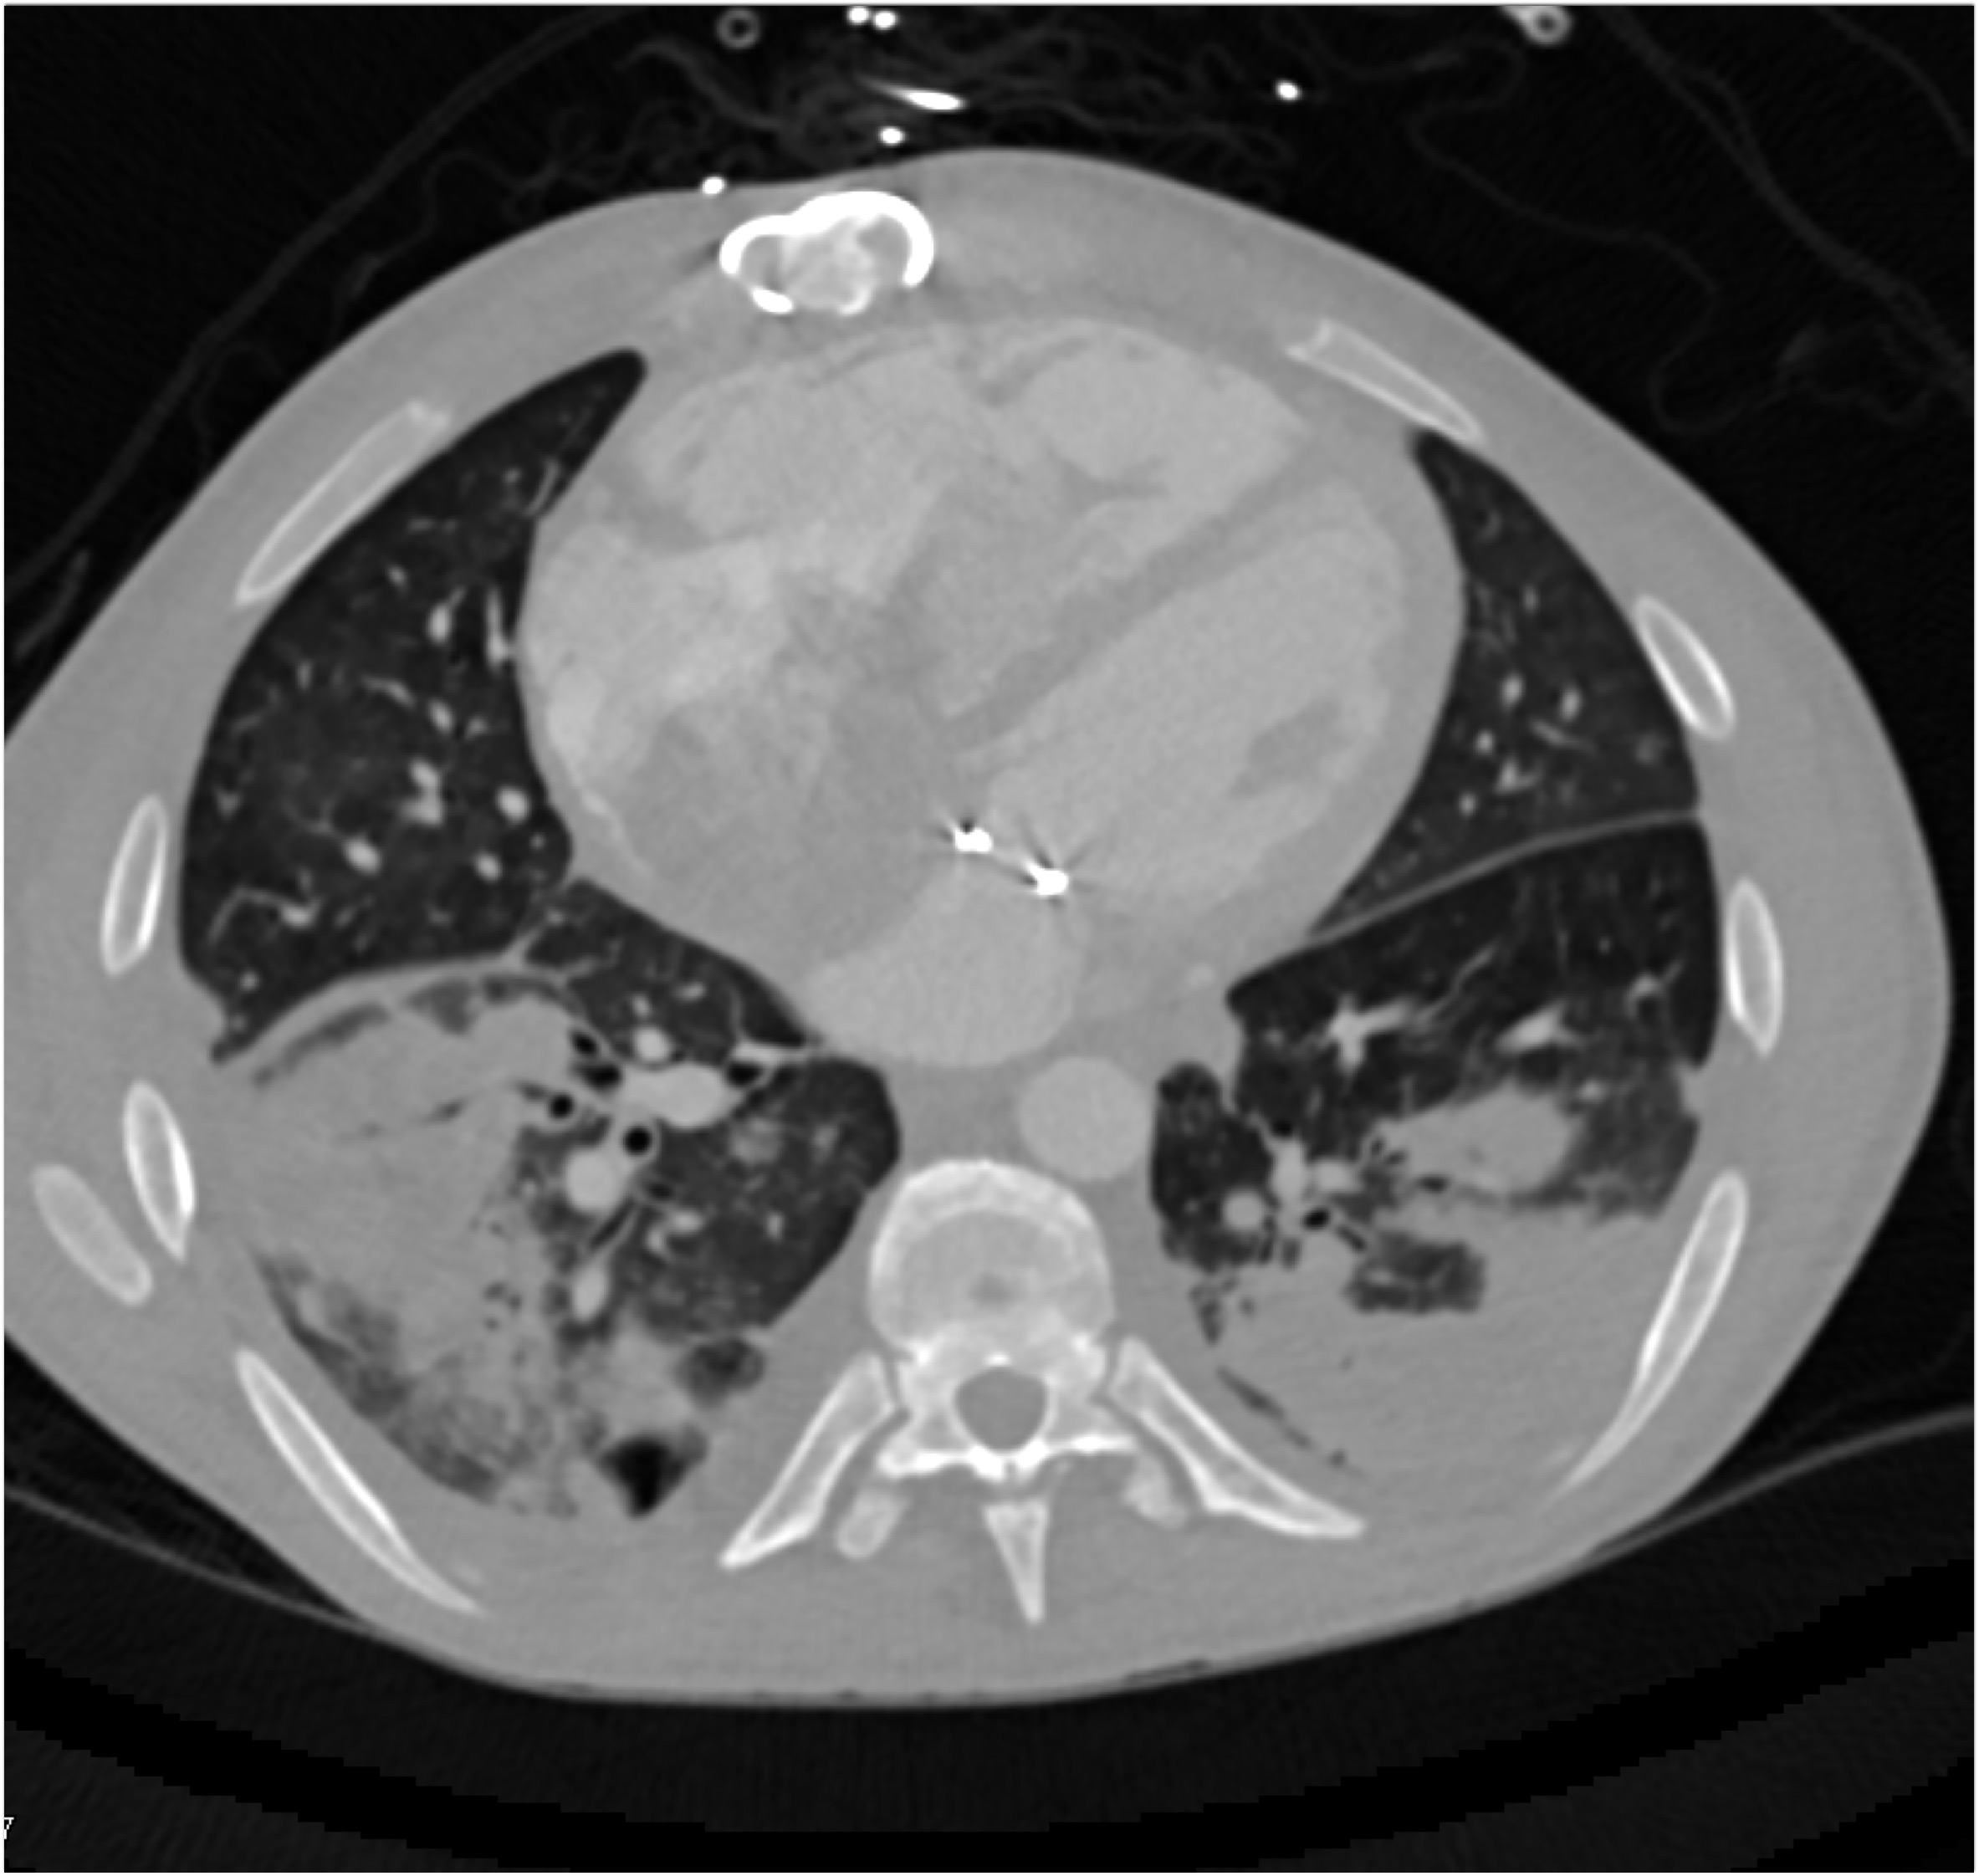

6) The most likely diagnosis in this case is?

vegetations in pulmonary valve

failed pulmonic valve

normal appearance of repaired pulmonary valve

abscess of the pulmonary artery